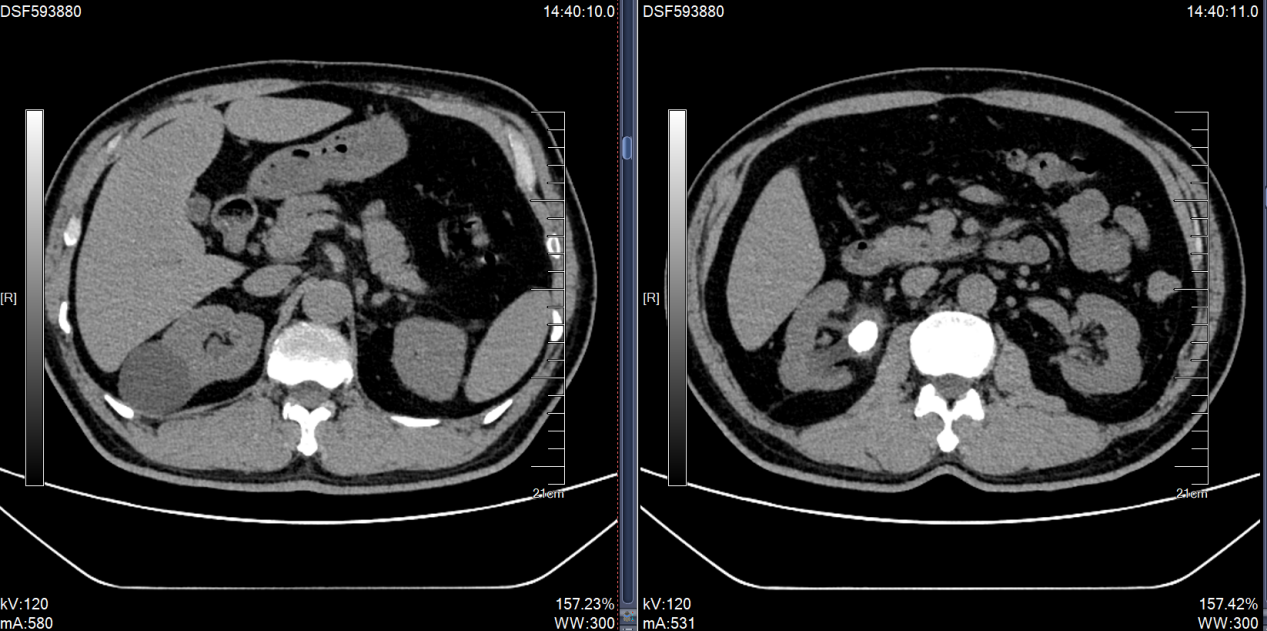

患者在外院检查发现:CT提示右肾多发结石,右侧肾盂及输尿管扩张积水。患者既往曾多次行输尿管镜手术,存在右输尿管狭窄病史。患者入院后浦金贤主任组织科室讨论指出,患者右肾下盏多发结石,且部分位于下盏小盏,角度刁钻,手术难度大,单一经皮肾镜或输尿管软镜难以完全清除结石。周守军主任带领结石团队全力准备手术,采取斜仰卧位经皮肾镜-输尿管软镜(PCNL-RIRS)双镜联合的手术方式,一期手术彻底清除结石,复查结石无残留,达成理想的治疗效果。